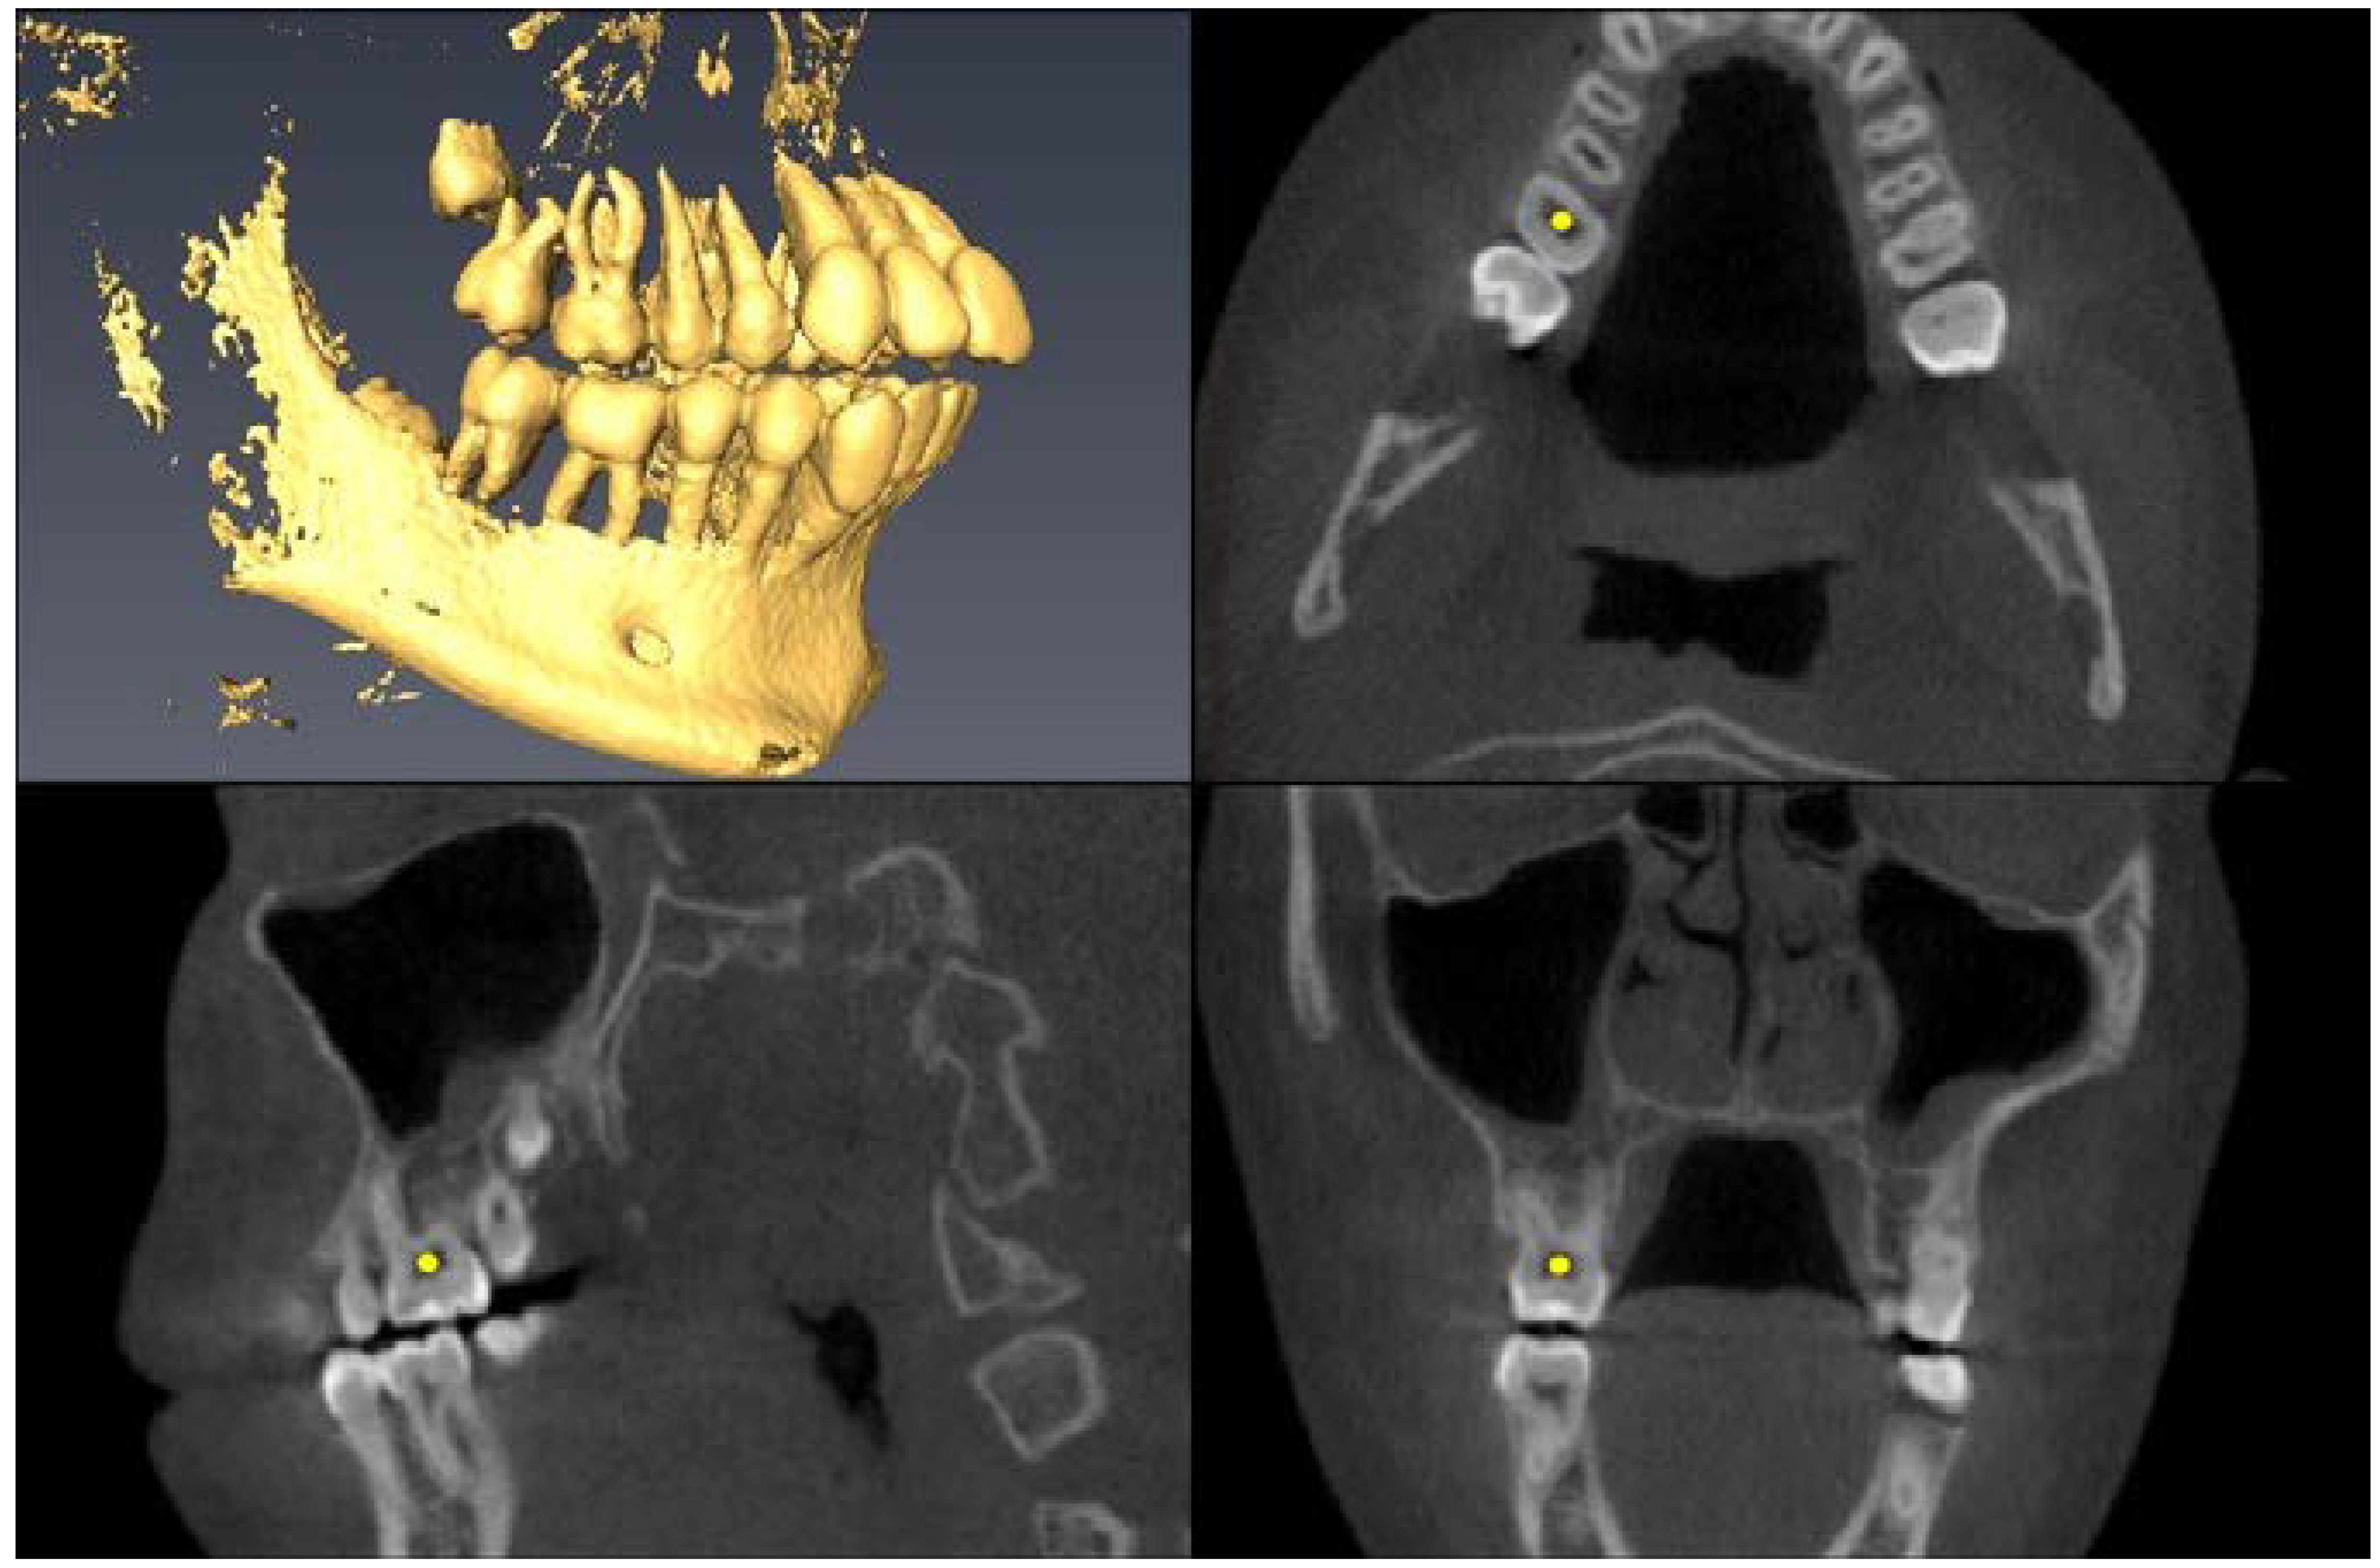

| Landmark Description | 3D View (Upper Left), Axial View (Upper Right), Sagittal View (Lower Left), Coronal View (Lower Right) |

|---|---|

| Upper First Molar Pulp Chamber =center of largest cross-sectional pulp chamber area | ![]() |